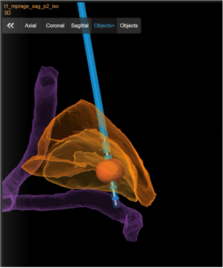

Spinalganglienstimulation („dorsal root ganglion“-Stimulation)

Neben der Rückenmarksstimulation ist es bei bestimmten chronischen Schmerzen möglich, ganz gezielt bestimmte Spinalganglien zu stimulieren. Das Spinalganglion ist ein Bündel aus Nervenkernen und Nervenfasern, das alle sensorischen und schmerzhaften Reize einer Nervenwurzel verarbeitet. Bei diesem Verfahren werden feine Elektroden direkt an das Spinalganglion eingesetzt. Wie bei der Rückenmarksstimulation werden die Elektroden durch einen Impulsgeber angesteuert, der unter die Haut implantiert wird. Die abgegebenen elektrischen Impulse hemmen die Schmerzweiterleitung. Diese Therapie findet Anwendung bei thorakalen Neuropathien (z.B. nach Mastektomie, Thorakotomie oder Herpes Zoster), bei Leistenschmerzen nach Leistenhernienoperationen, bei Schmerzen nach Operationen am Knie, Fuß, Hüft Hand oder Schulter sowie beim komplexen regionalen Schmerzsyndrom oder Phantom- und Stumpfschmerzen nach Amputationen. Auch bei der Spinalganglienstimulation bleiben die Nervenstrukturen erhalten, sodass die Stimulation jederzeit rückgängig gemacht werden kann. Die Einstellungen des Impulsgebers lassen sich von außen – auch durch die Patient:innen – verändern, sodass die Stimulation jederzeit an die Bedürfnisse der Patient:innen angepasst werden kann.